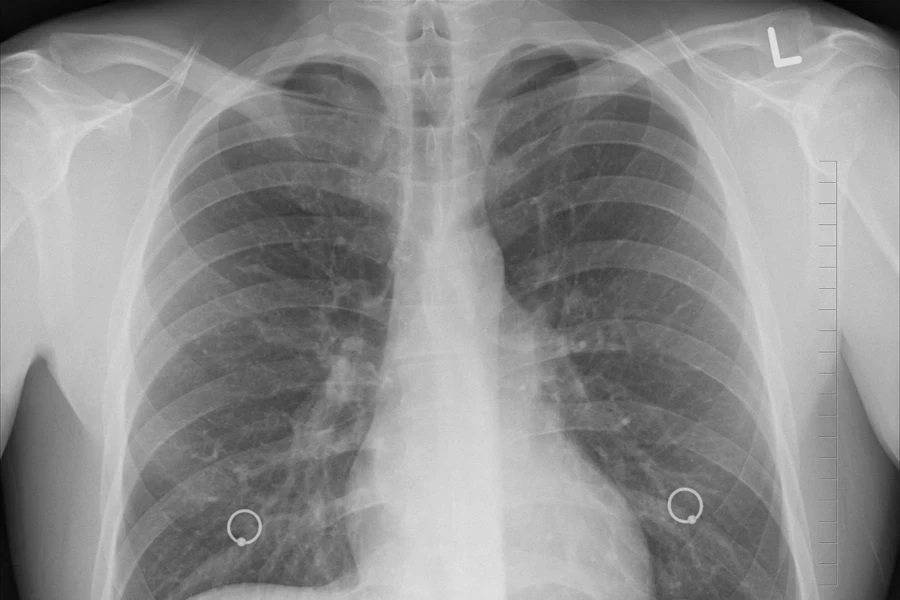

В клиниках Москвы начала работать разработанная в Калуге технология комплексного анализа компьютерной томографии органов внутри грудной клетки с применением искусственного интеллекта, сообщает ТАСС.

Она позволяет проводить анализ компьютерных томографий и обнаруживать признаки 7 различных патологий, включая опухоли, коронавирус, травмы позвоночника, жидкость в плевральных областях, ишемическую болезнь сердца, аневризму аорты и расширение легочного ствола.